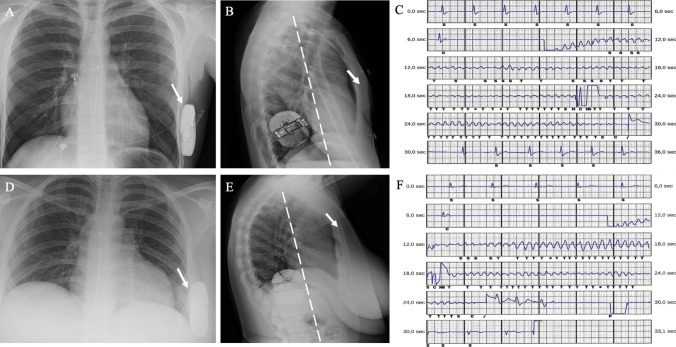

目的:本研究旨在评估采用肌间(IM)双切口技术进行皮下植入式心律转复除颤器(S-ICD)植入术的患者在 3 年随访期间的疗效。方法:研究对象包括采用 IM 双切口技术进行 S-ICD 植入术的 105 名连续患者(79 名男性;中位年龄 50 [13-77] 岁)。研究的综合主要终点包括设备相关并发症和不适当电击(IAS)。次要终点包括主要终点的各个组成部分、任何原因导致的死亡、适当的治疗、主要不良心脏事件、因心力衰竭住院以及心脏移植:根据 PRAETORIAN 评分,99 名患者(94.3%)的转换失败风险被归类为低,6 名患者(5.7%)的转换失败风险被归类为中。在中位随访39(16-53)个月期间,10名患者(9.5%)出现了与设备相关的并发症,9名患者(8.5%)报告了IAS。最常见的并发症是导联相关并发症(5 例患者,4.7%),包括 2 例导联失效(1.9%)。有 2 例患者(1.9%)报告了口袋并发症。心外超感(3.8%)是导致 IAS 的主要原因。没有记录到 T 波超感应事件。12 名患者(11.4%)经历了适当的电击。八名患者(7.6%)在随访期间死亡。IAS或设备相关并发症对死亡率没有影响:随访3年期间,设备相关并发症和IAS的总发生率分别为9.5%和8.5%。根据我们的研究结果,IM 双切口技术可实现装置的最佳定位,达到较低的 PRAETORIAN 评分和较高的转换率。IM双切口技术可降低囊袋并发症的发生率,将并发症的类型转向导联相关并发症,这是最常见的并发症。IM双切口技术似乎不会影响IAS的发生。并发症的处理是安全的,不会对结果产生影响。

Results: According to the PRAETORIAN score, the risk of conversion failure was classified as low in 99 patients (94.3%), intermediate in 6 (5.7%).Ventricular fibrillation was successfully converted at ≤65 J in 97.4% of patients. During a median follow-up of 39 (16-53) months, 10 patients (9.5%) experienced device-related complications, and 9 (8.5%) patients reported IAS. Lead-associated complications were the most common (5 patients, 4.7%), including 2 cases of lead failure (1.9%). Pocket complications were reported in 2 patients (1.9%). Extra-cardiac oversensing (3.8%) represented the leading cause of IAS. No T-wave oversensing episodes were recorded. Twelve patients (11.4%) experienced appropriate shocks. Eight patients (7.6%) died during follow-up. IAS or device-related complications did not impact on mortality.

Conclusions: The overall device-related complications and IAS rates over 3 years of follow-up were 9.5% and 8.5%, respectively. According to our findings, the IM two-incision technique allows for optimal positioning of the device achieving a low PRAETORIAN score with a high conversion rate. IM two-incision technique allows low incidence of pocket complications, shifting the type of complications towards lead-related complications, which represent the most common complications. The IM two-incision technique would not seem to impact the occurrence of IAS. Management of complications are safe without impact on the outcome.